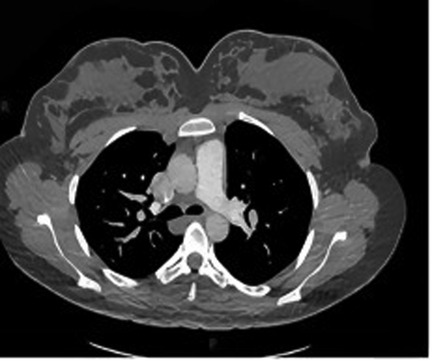

A 24-year-old woman was admitted at 27 + 6 weeks of gestation due to recurrent hemoptysis. She reported a sudden onset of coughing during sleep without any identifiable trigger, followed by expectoration of approximately 20 ml of bright red blood. The episode was accompanied by orthopnea, but there were no symptoms of chest pain, dyspnea, or fever. The patient had no significant past medical history, including no hypertension, coronary artery disease, diabetes mellitus, hyperthyroidism, or exposure to toxins or radiation. On admission, physical examination revealed bilateral lower limb edema. Her vital signs were: temperature 37.4 ℃, heart rate 126 bpm, respiratory rate 20 /min, blood pressure 120/70 mmHg, and oxygen saturation 93% under oxygen therapy (Oxygen inhalation state). Transthoracic echocardiography with contrast revealed a positive right heart contrast study, suggesting the presence of a PAVM (Figure 1). Subsequent contrast-enhanced pulmonary artery CT further confirmed the diagnosis, indicating a pulmonary arteriovenous malformation in the upper lobe of the left lung, suggesting by localized pulmonary atelectasis (Figure 2). A multidisciplinary consultation was conducted. Based on the patient's history, physical findings, and auxiliary tests, the final diagnoses were: pregnancy complicated with pulmonary hemorrhage, pulmonary arteriovenous fistula, pulmonary infection, congenital pulmonary vascular malformation, pregnancy with hypothyroidism, type I respiratory failure, pregnancy with sinus tachycardia, hypokalemia, and respiratory alkalosis.

Figure 2. One or more enlarged, tortuous soft-tissue density structures are observed traversing the pulmonary parenchyma in the right hilar region (left side of the image). These structures demonstrate an atypical course and morphology inconsistent with normal pulmonary arteries or veins, strongly suggestive of a pulmonary arteriovenous fistula (PAVF).